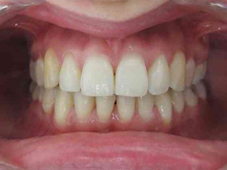

Présentation cas clinique :

Avant traitement

Après traitement